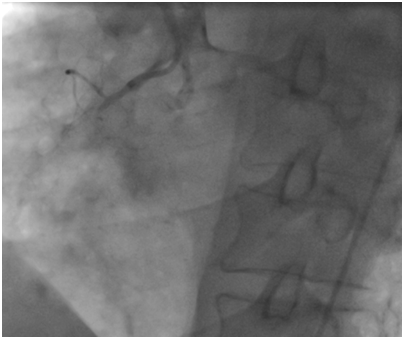

The first case

A 53year-old male without cardiovascular risk factor was admitted to our hospital in 2005 due to an inferior AMI. The culprit lesion was thrombotic occlusion of proximal right coronary artery (RCA). Primary percutaneous coronary intervention to RCA with a BMS (3.00x24mm; Liberté®; Boston scientific, Natick, Massachusetts) was done with an excellent result. No post-dilatation was needed. Dual antiplatet therapy was prescribed for one month (Clopidogrel 75mg once a day). Then; aspirin (ASA) was prescript alone for life. Eight years later, he suffered from a severe chest pain relevant to a recurrent inferior AMI. Hence, he was immediately referred for a primary angioplasty. In-stent huge thrombosis was located in the proximal edge of the stent of the RCA. IC stent® (Siemens Healthcare GmbHErlangen, Germany) had showed an underdeployment of the stent. Then, a predilatation with a non compliant Balloon had restored a TIMI III flow. He was discharged five days later with a daily 75mg of clopidogrel for 12months and 100mg of ASA associated daily for life (Figure 1-3).

Figure 2 Underdeployment of stent on the IC stent®.